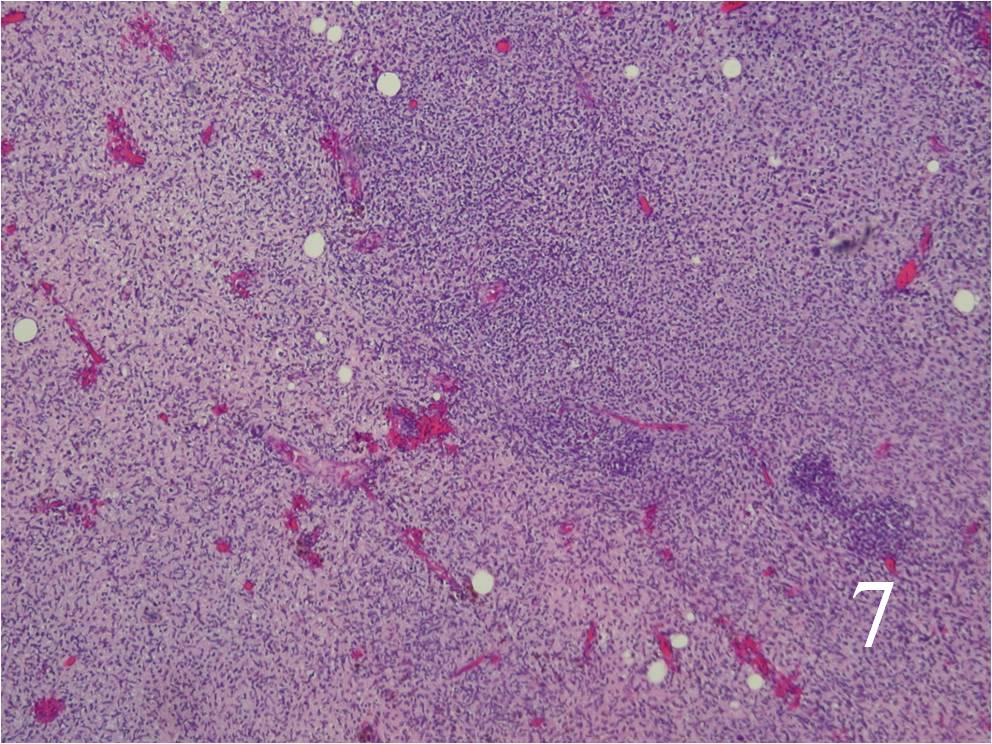

- Spindle cells with markedly irregular contours (Fig. 7, 8)

Fig. 7 Low power and high power (Fig. 8) magnification on H&E staining shows a spindle cell neoplasm with high cellularity, abnormal mitotic features and nuclear atypia. The cells are arranged in a somewhat fascicular manner.